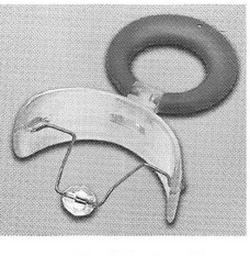

Rysunek przedstawia narzędzie do

A. zakładania gumek separacyjnych.

B. umocowania klamer koferdamu.

C. zakładania pierścieni ortodontycznych.

D. formowania pętli drucianych.